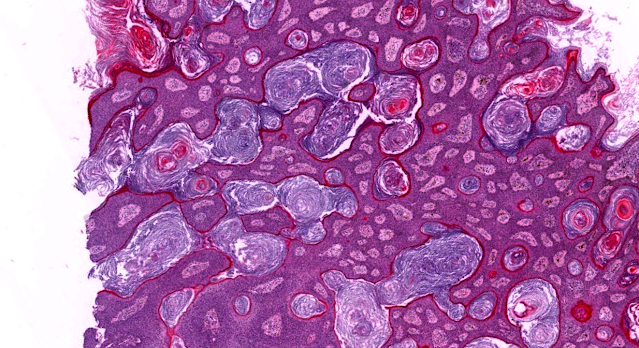

Dermatopathology Case 247 Get link Facebook X Pinterest Email Other Apps July 21, 2022 Skin lesion. Spot diagnosis. Answer Get link Facebook X Pinterest Email Other Apps Comments